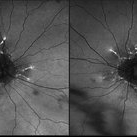

Purtscher's Retinopathy

Mar 30 2018 by Olivia Rainey

Bilateral OCTS of a 21-year-old female with Purtscher's Retinopathy affecting both eyes. Patient developed acute pancreatitis triggered by hypercalcemia and likely increased alcohol consumption.

Photographer: Olivia Rainey

Imaging device: Spectralis

Condition/keywords: acute pancreatitis, bilateral, optical coherence tomography (OCT), Purtscher's retinopathy